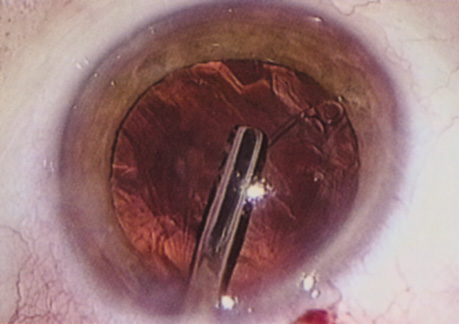

HYDRODISSECTION Hydrodissection can be performed after the surgeon has successfully completed capsulorrhexis.97 If the capsulorrhexis is not intact, fluid forced around the interior of the capsule may cause the bag to splay open. With capsulorrhexis, hydrodissection is a safe and extremely useful maneuver. Hydrodissection can be thought of as two maneuvers: hydrodelineation and cortical cleaving hydrodissection. By placing a 27-gauge cannula on a syringe filled with balanced saline solution (BSS), the surgeon can direct fluid beneath the residual anterior capsular rim to create a cleavage plane. Depending on the direction the fluid wave takes, different lamellae of the cataract will be separated. Hydrodelineation is the term used when the cleavage plane separates the adult nucleus from the fetal nucleus or the adult nucleus from the more peripheral epinucleus. Hydrodelineation often results in the characteristic golden ring sign (Fig. 11). Cortical cleavage occurs when the cortex is separated from the capsular bag (Fig. 12). Finding the cortical cleavage plane may be facilitated by gently lifting the capsular margin away from the cortex with the BSS cannula before injecting. Several small bursts of fluid allow the surgeon to monitor progress of the fluid wave. When dealing with a soft nucleus, the authors strive to perform true cortical cleaving hydrodissection. For a hard nucleus, hydrodelineation allows manipulation of less of the nuclear bulk, although the remaining epinuclear shell must be addressed in an additional step. Hydrodelineation is particularly useful if the nucleus is not freely mobile after cortical cleaving hydrodissection.